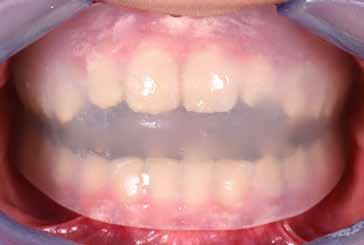

B.M. Bambina di sei anni e mezzo, con malocclusione scheletrica di II Classe, deep-bite over-jet elevato, lieve contrazione dell’arcata superiore, alterazione dell’eruzione dell’elemento dentale 21.

Fig. 122 > Immagine intraorale frontale.